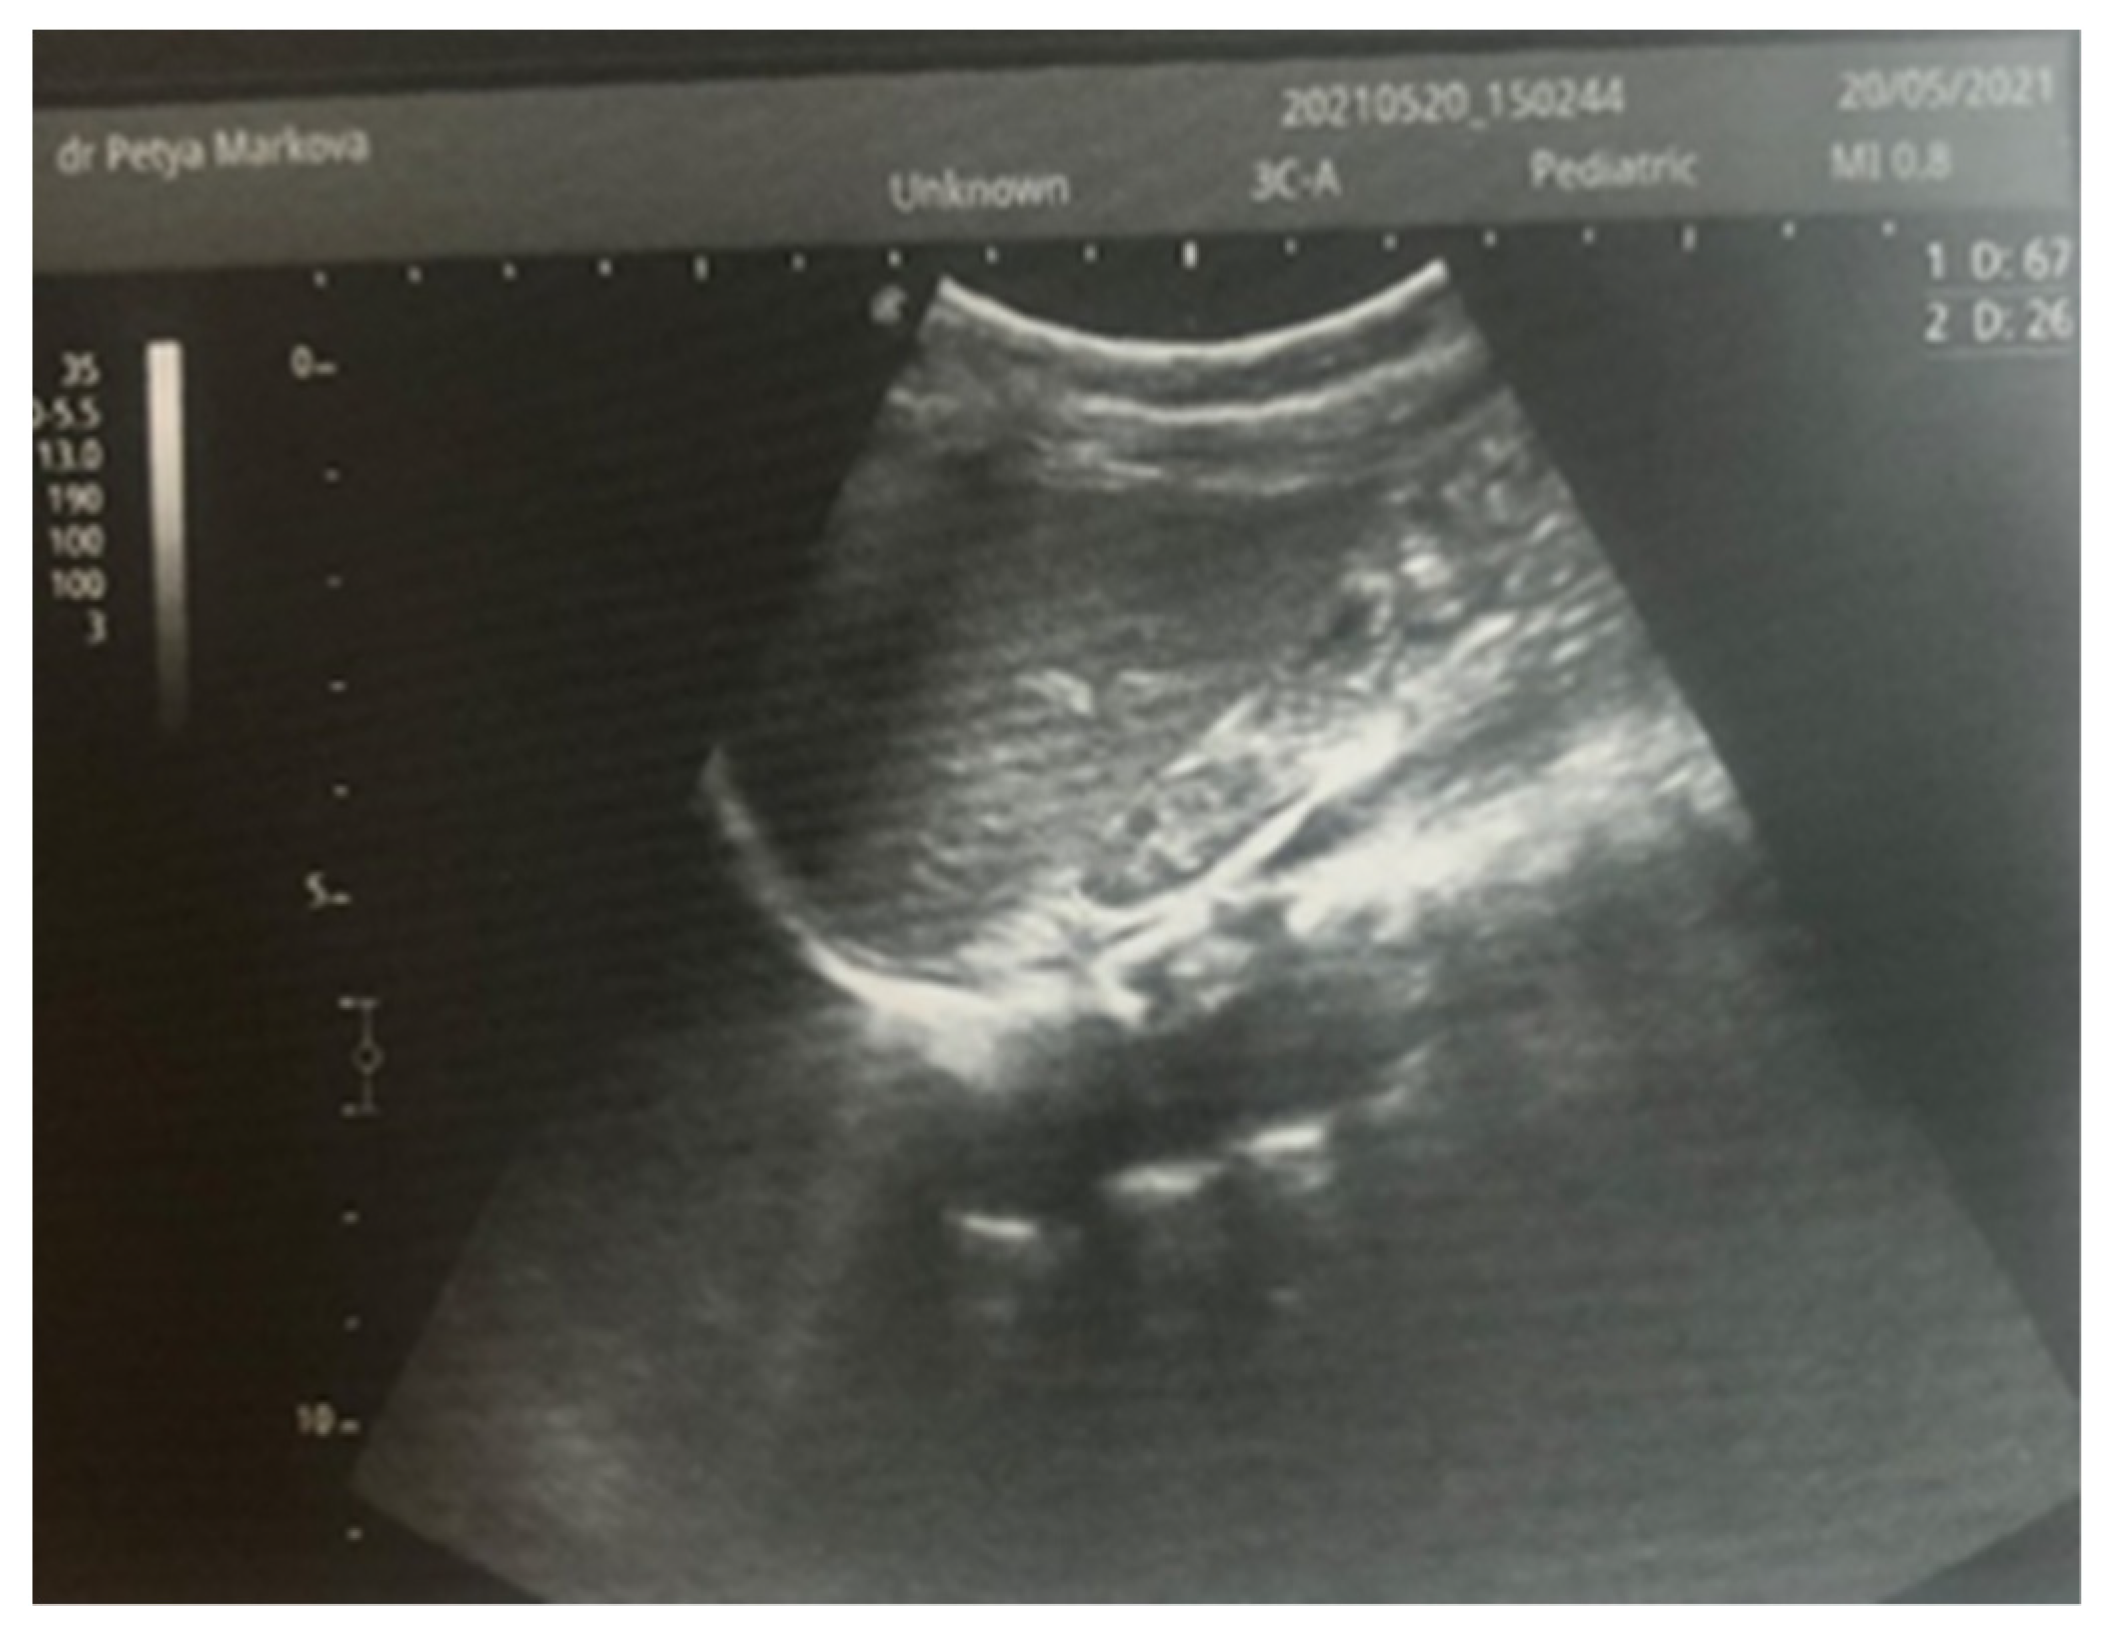

After admission to the NICU, the neonate was found febrile, with symptoms of multiple organ failure: respiratory system failure requiring treatment with Curosurf and mechanical ventilation; renal failure with symptoms of oliguria, macroscopic hematuria, and an increase in nitrogen waste products; the manifestation of neurological symptoms—muscular hypertonia and hyperreflexia, increased convulsive readiness with frequent spontaneous and provoked clonuses of the limbs. The blood tests revealed inflammatory activity—increased CRP and evidence of early nonconjugated hyperbilirubinemia. An abdominal ultrasound examination, performed 2 h after birth, found an enlarged right kidney with a longitudinal size of 6.1 cm, swollen parenchyma with a thickness of 1.8 cm, and increased echogenicity with the presence of interlobar hyperechogenic spikes—an image characteristic of the early phase of renal vein thrombosis. The left kidney—with a longitudinal size of 4.1 cm—preserved the topic, size, and echogenicity of the parenchyma, without drainage disorders, see Figure 1 and Figure 2.

Figure 2. Left kidney image taken in the 2nd hour after birth—the topic, size, and echogenicity of the parenchyma are preserved, without drainage disorders.